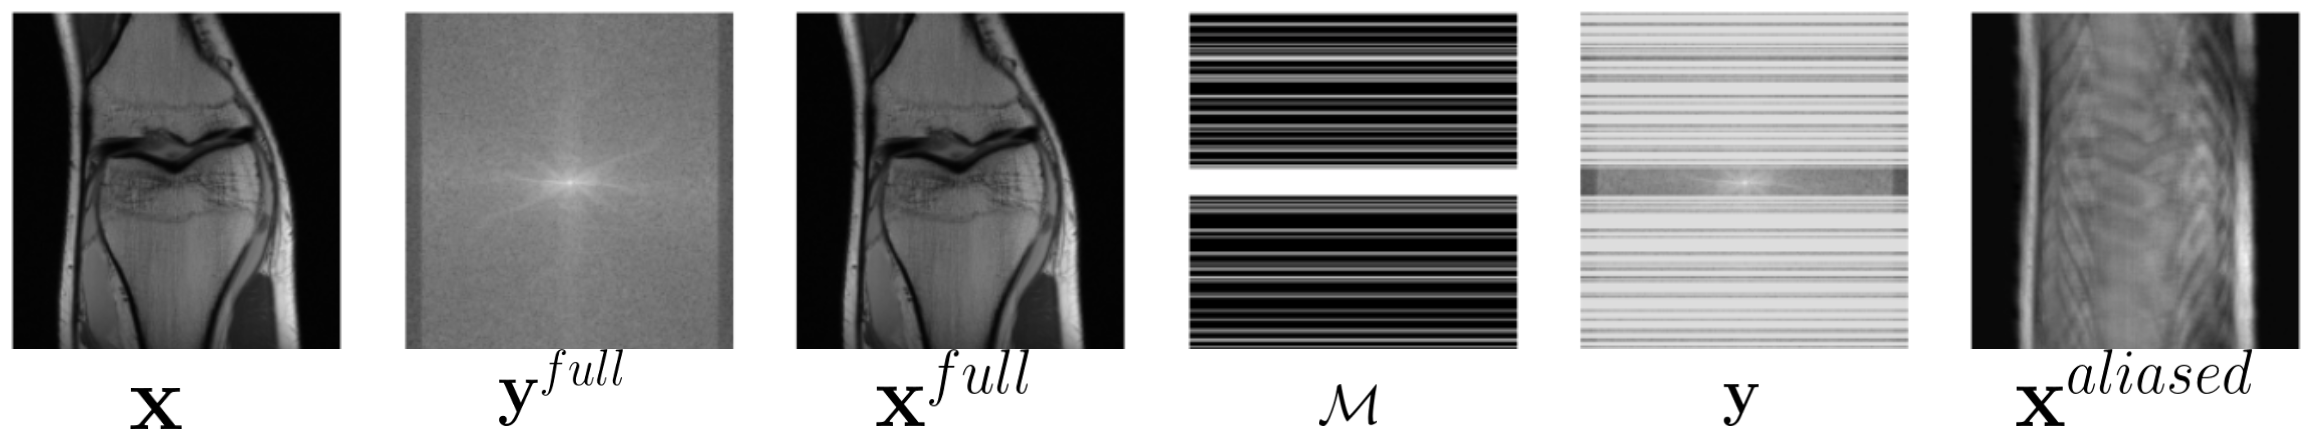

Modern MR scanners support parallel acquisition using an array of overlapping receiver coils modulated by their sensitivities . So Eqn. 1 changes to: , where is the number of receiver coils. We use for the undersampled k-space measurement coming from the receiver coil. To speed up the data acquisition process, multiple lines of k-space data (for cartesian sampling) are skipped using a binary sampling mask that selects a subset of k-space lines from in the phase encoding direction:

An example of , y, is shown in Fig 1.